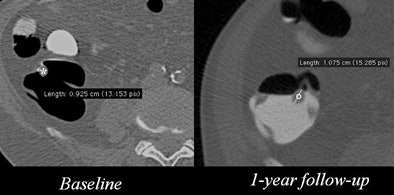

VC surveillance of patients with C-RADS C-2 findings

There was no significant difference between the techniques used at any time interval, as well as no difference between the rate of preference for CTC or optical colonoscopy as a follow-up technique.

| CTC is depicted in green; optical colonoscopy is in red. Faggioni et al analyzed surveillance data using the Chi-square test with Yates' correction for continuity. The results showed that most patients chose follow-up with either CTC or optical colonoscopy before 18 months rather than later (χ2 = 12.66, p = 0.0004, and χ2 = 12.53, p = 0.0004, respectively). With either CTC or optical colonoscopy, no statistically significant difference was found between the ratios of patients undergoing follow-up before 18 months and from 18 months onward (χ2 = 0.01, p = 0.9203). Image courtesy of Dr. Lorenzo Faggioni. |

"But there was a clear trend of patients who had an early follow-up," Faggioni said. "A substantial fraction of surveillance patients prefer to undergo immediate optical colonoscopy and polyp removal rather than follow-up with either technique. The majority of patients accepting follow-up are willing to wait for a maximum of 12 months, so an 18-month follow-up period does not seem reasonable."